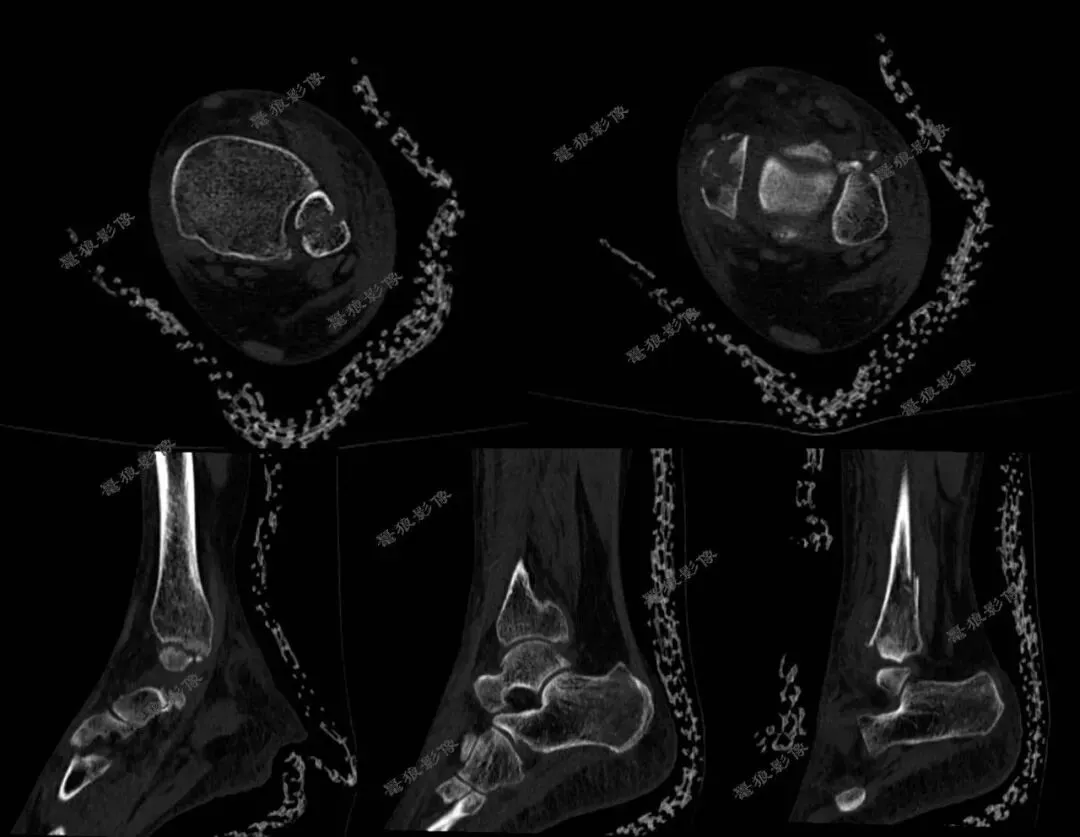

F,62y。跌伤左踝部肿痛活动受限3小时余。

术前CT:

1、左三踝粉碎性骨折,胫距关节半脱位,踝关节软组织肿胀;

2、左足舟状骨、内侧楔骨、第1-4跖骨近端骨折。

术后X线:

1、左三踝骨折内固定术后;

2、考虑左足第3、4跖骨基底部骨折可能;

请结合临床及术前CT。